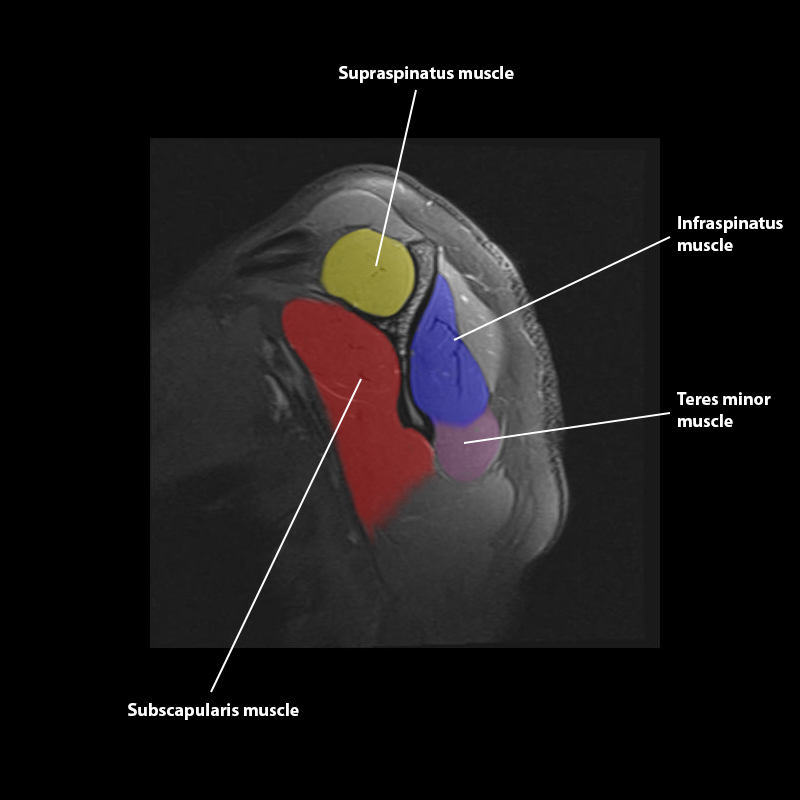

Shoulder MRI Anatomy